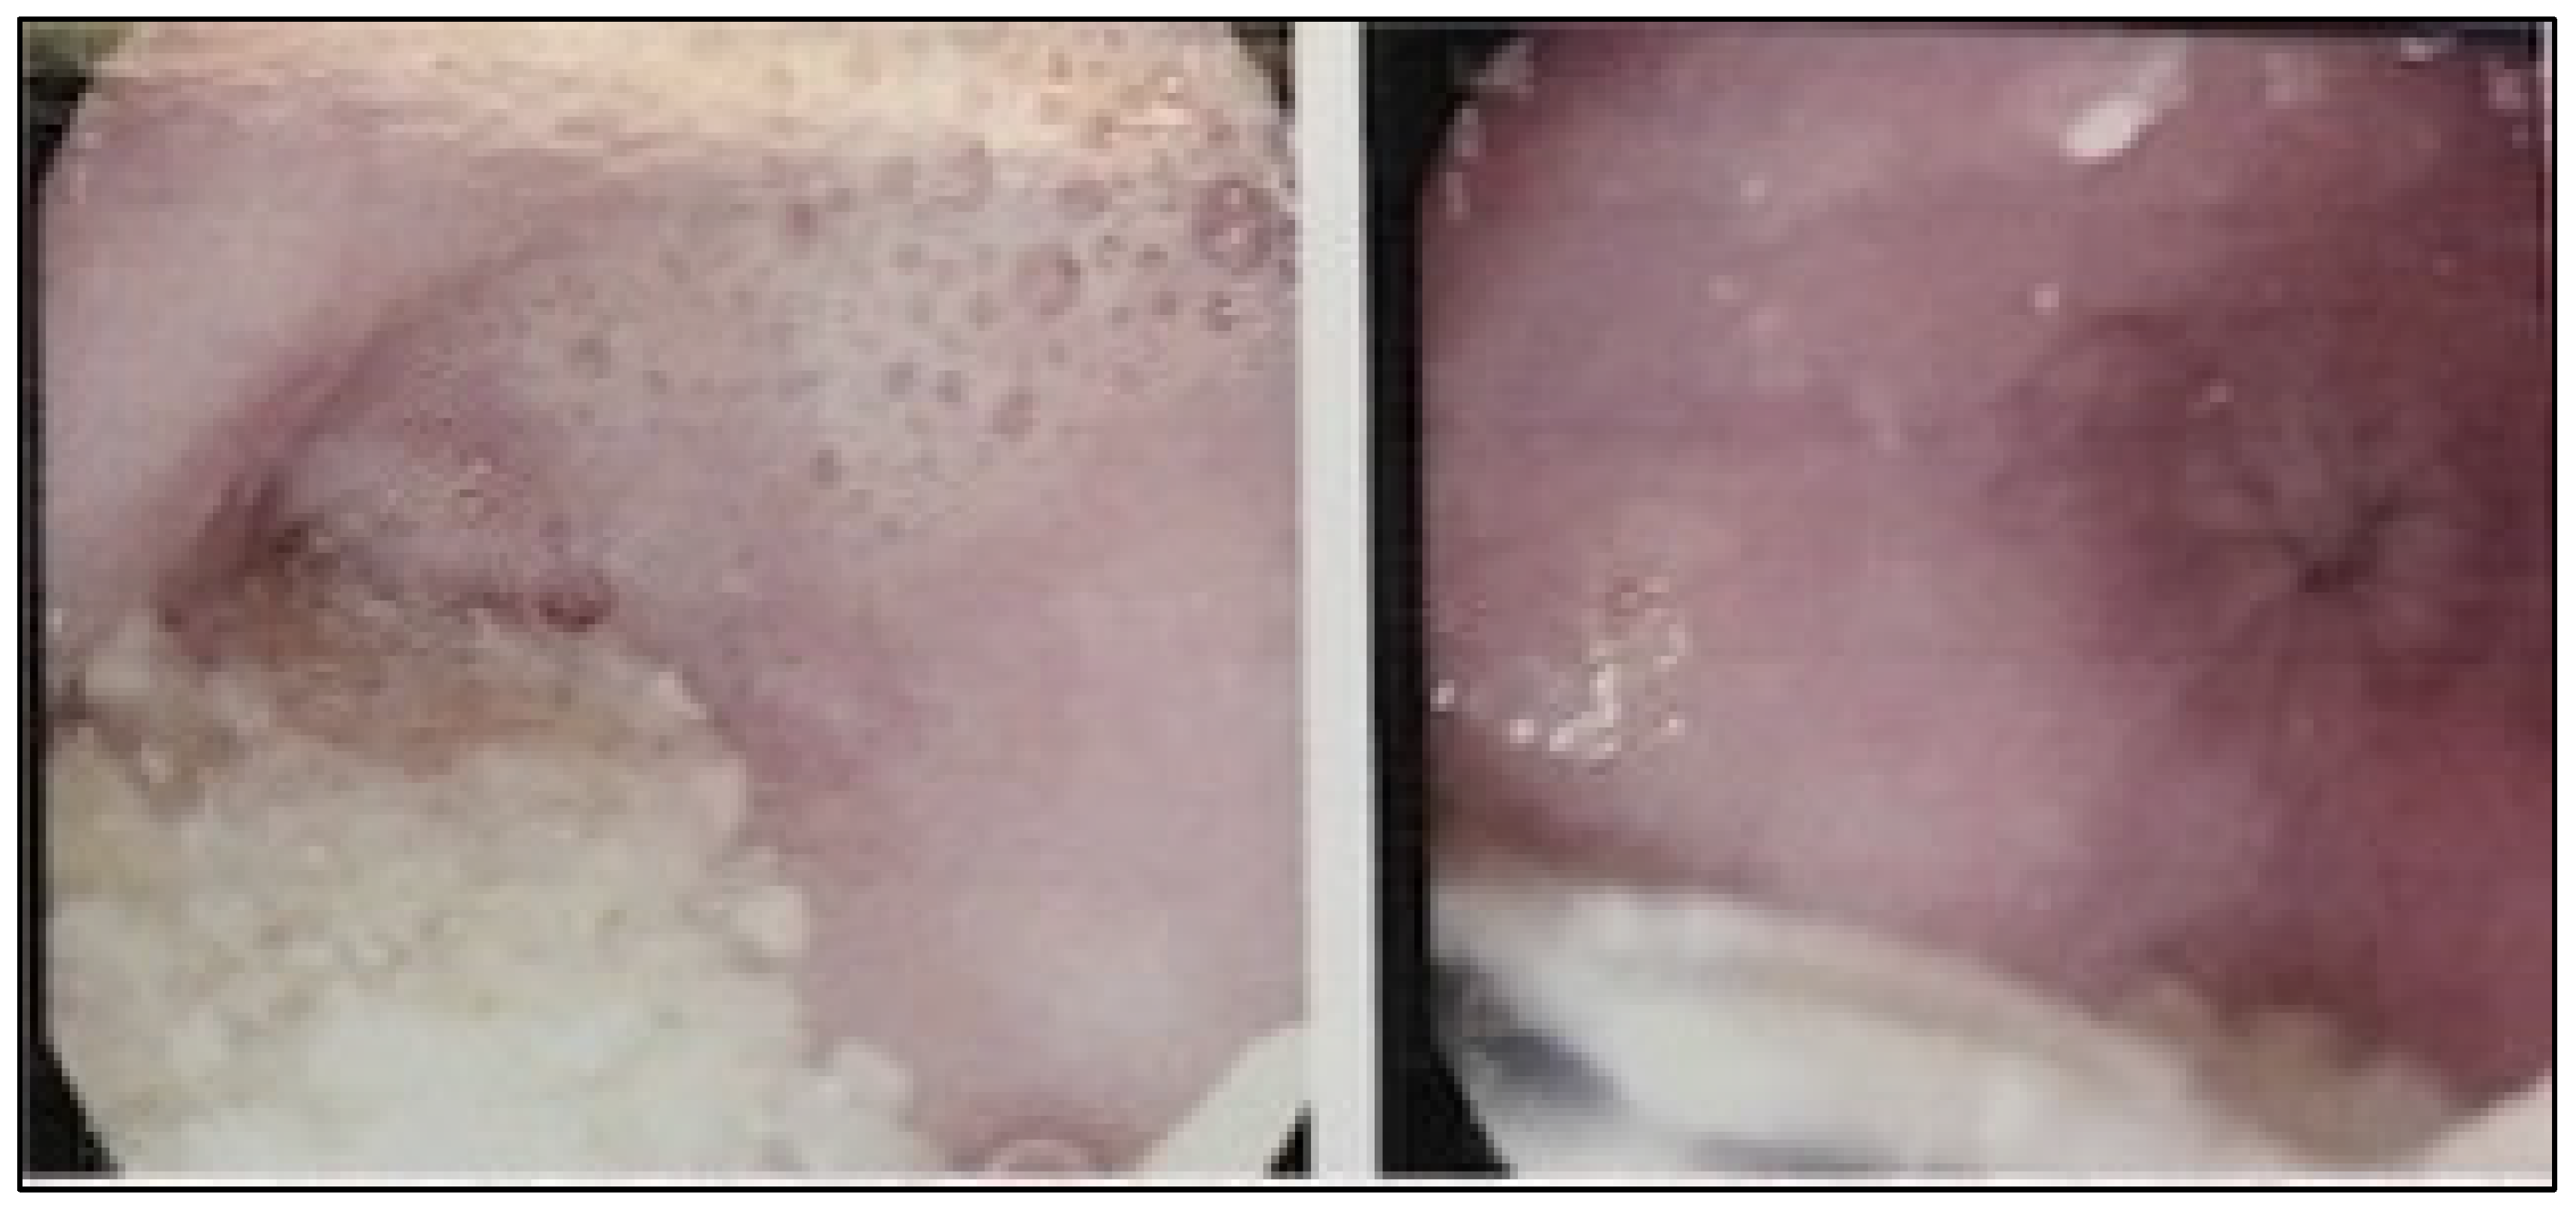

First, a pandendoscopy was performed (Figure 1A,B), showing an increase in the esophageal diameter in its 3 thirds with abundant food debris. A retentive esophagus with a diagnostic impression of probable achalasia was reported. Afterwards, manometry was indicated, identifying a mean residual pressure in the lower esophageal sphincter of 29.1 mmHg. Regarding the upper esophageal sphincter, a mean basal pressure of 133.9 mmHg was reported, with a relaxation time of 1,092ms and a recovery time of 849 ms, compatible with a diagnosis of achalasia subtype II of the Chicago classification ver 3.0 (Figure 2). Finally, an esophagogastroduodenal series was performed (Figure 3A,B) where typical pencil-point images are found. She was scheduled by the surgical service for the performance of a Heller cardiomyotomy with laparoscopic Roux-en-Y Bypass, choosing this technique instead of fundoplication due to the surgical history of gastric sleeve.

Figure 1. A and 1B. Panendoscopy. There is an increase in esophageal diameter and abundant food debris.